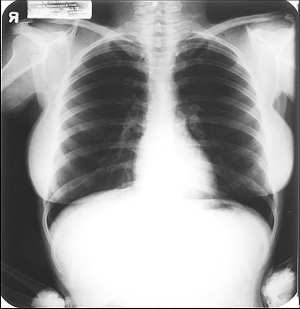

梦露生前一张X光片将拍卖 价值近40万美元

梦露生前X光片 现代快报 图片 中新网4月14日电 据台湾今日新闻消息,好莱坞性感女星玛丽莲梦露生前的一张X光片即将举行拍卖。 报道称,这张X光片是1954年时,梦露在洛杉矶Cedars of Lebanon医院里拍下的。据悉,此张X光片可望以38万4000美元左右的售价拍卖出...查看详情